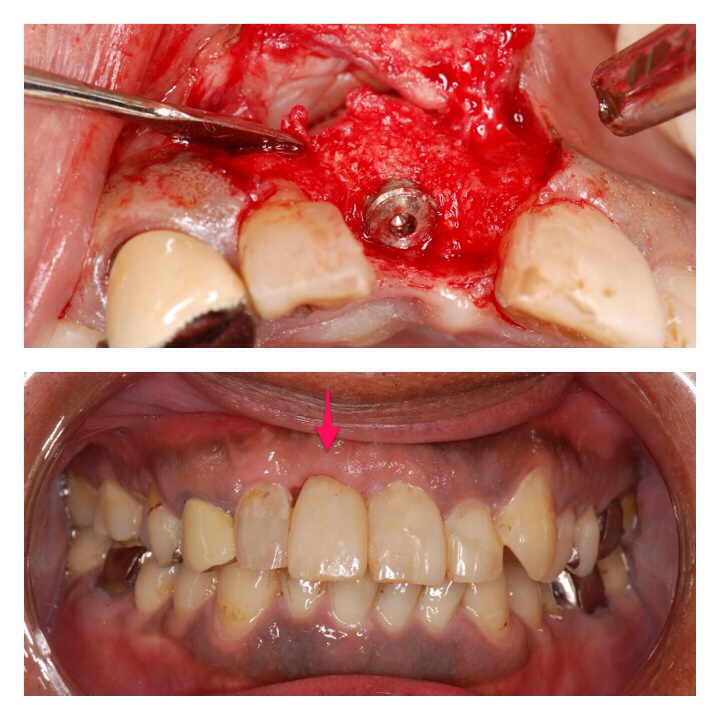

インプラント症例2

前歯のケースです。インプラント治療と分からないくらい他の歯に馴染んでいます